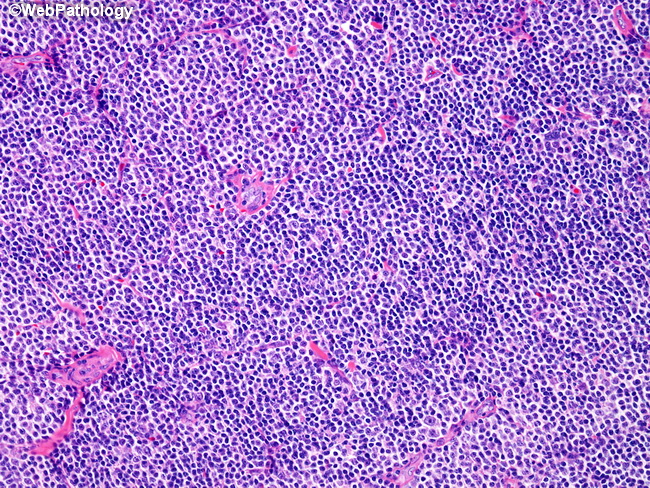

Микропрепараты: Лимфогранулематоз и Нодулярный Склероз